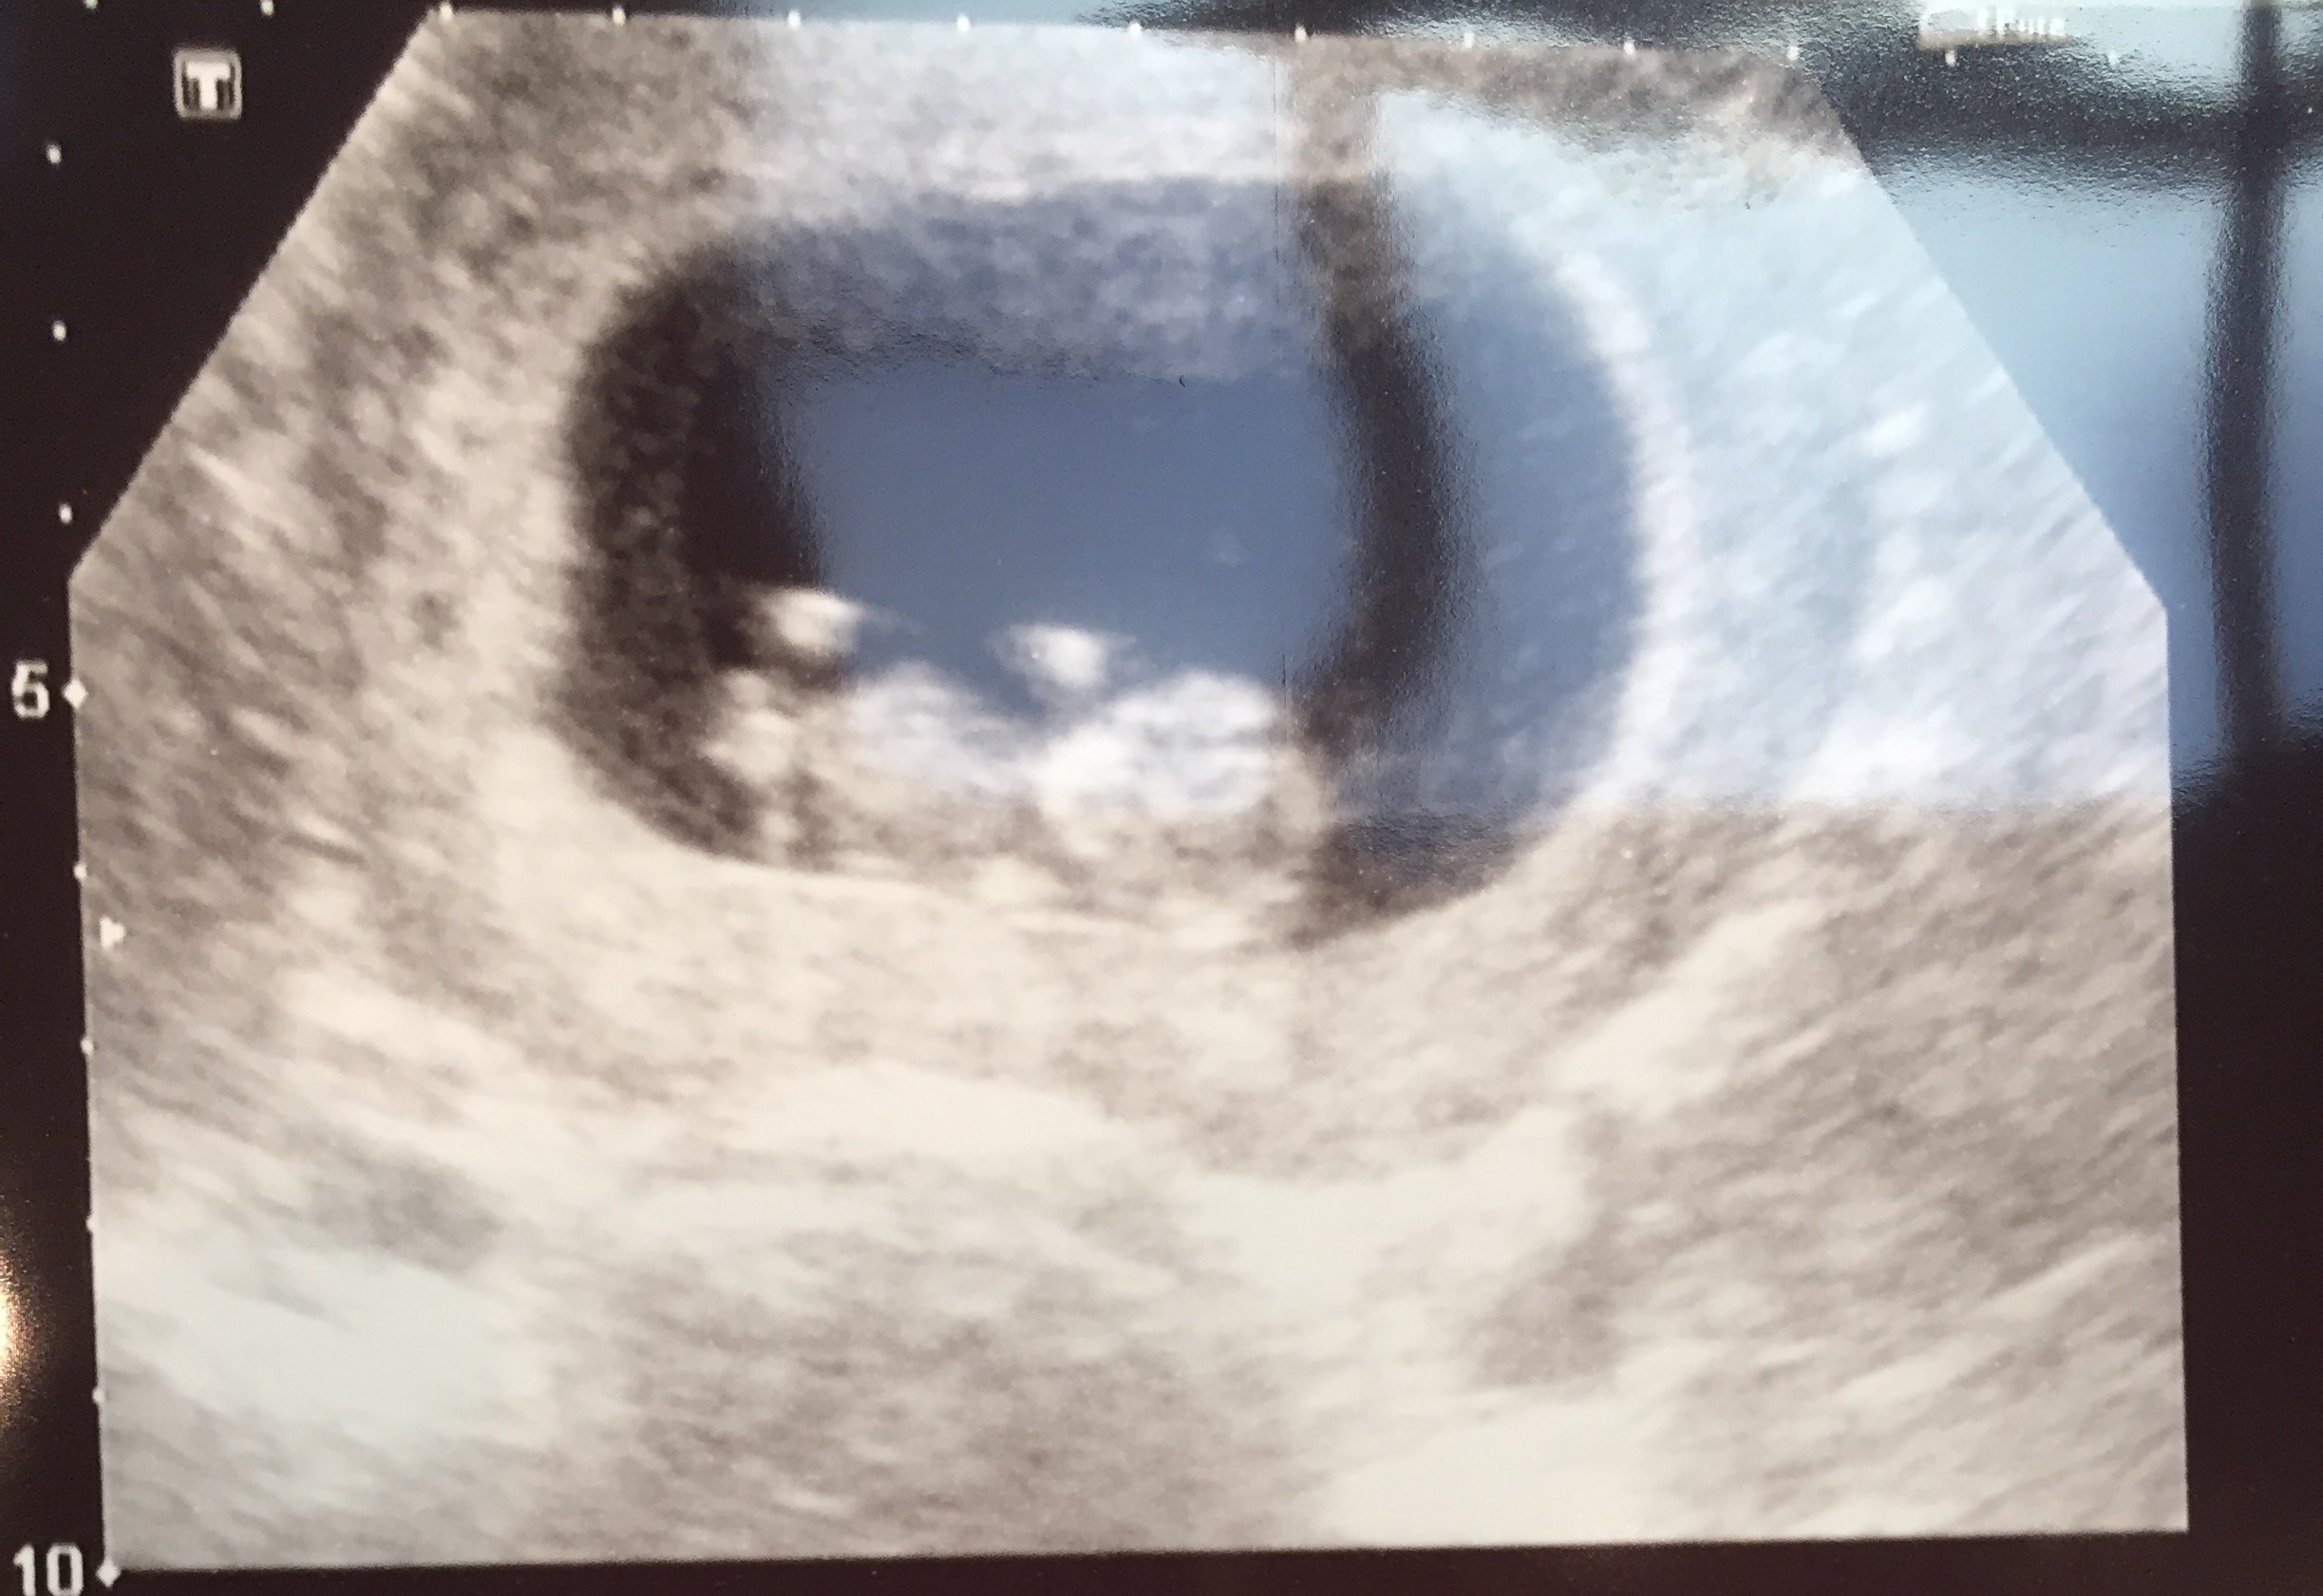

Any guesses? 11 week ultra sound picAttachment 31812

No nub and too early for guessing, sorry.